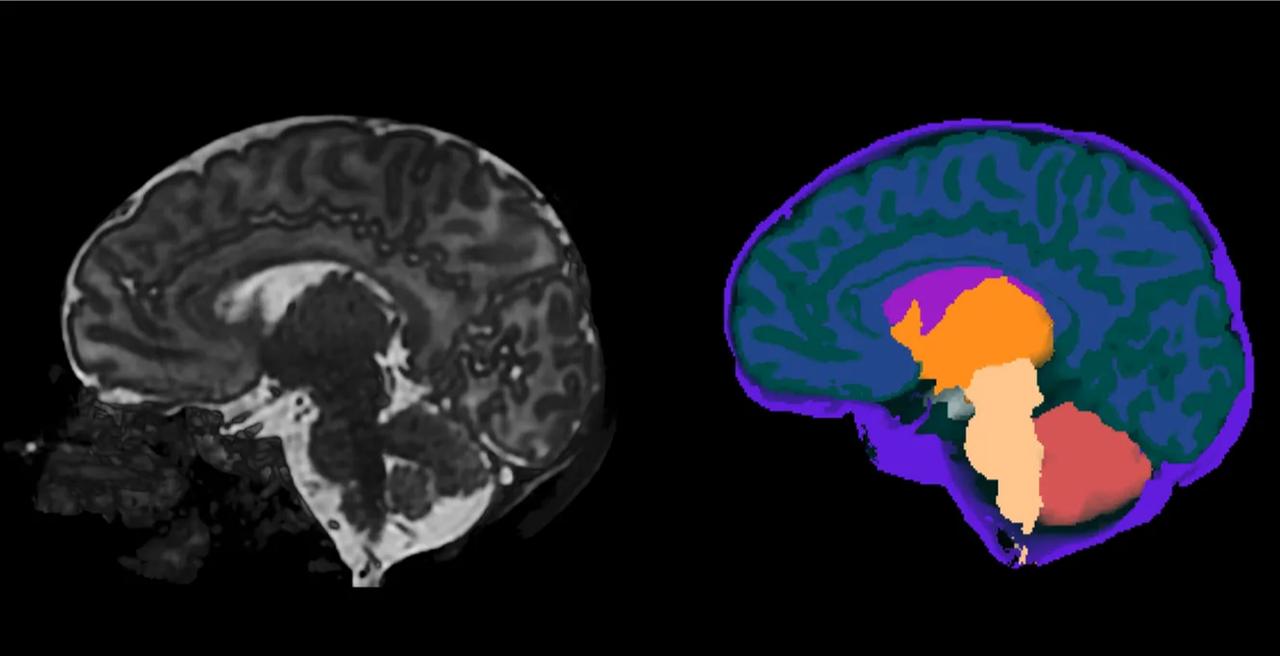

High-resolution neonatal brain MRI from the Developing Human Connectome Project, alongside a processed image segmenting different types of intracranial tissue. (Image via King's College London)